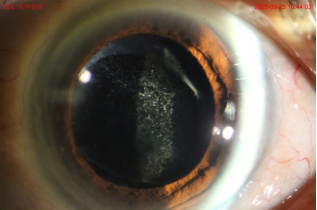

常有病人抱怨“醫(yī)生,我已經(jīng)做過白內(nèi)障手術(shù)了,為什么視力又模糊了,白內(nèi)障復(fù)發(fā)了嗎?”。其實白內(nèi)障摘除術(shù)已將原本混濁的晶狀體永久性移除,本身不會復(fù)發(fā),再次模糊是因為放人工晶體薄如蟬翼的“袋子”臟了。由于手術(shù)中會有一些晶狀體上皮細(xì)胞殘留在這個“袋子”上,隨著時間的推移,這些細(xì)胞會增殖、遷移到“袋子”的中央?yún)^(qū)域,并逐漸變得混濁、起皺,就像玻璃上蒙上一層灰。

患者出現(xiàn)手術(shù)前一樣的視力模糊感,這種病稱為“后發(fā)障”。從術(shù)后數(shù)月至數(shù)年均有可能發(fā)生。目前,YAG激光晶體后囊膜切開術(shù)可以把晶體的囊膜,即那層模糊的膜,打一個4-5mm的圓孔,去除模糊的囊膜,讓視力變得清晰。